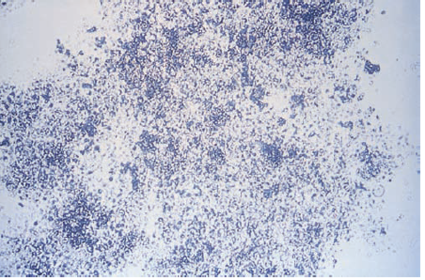

| Eosinophils (Hansel stained) | |